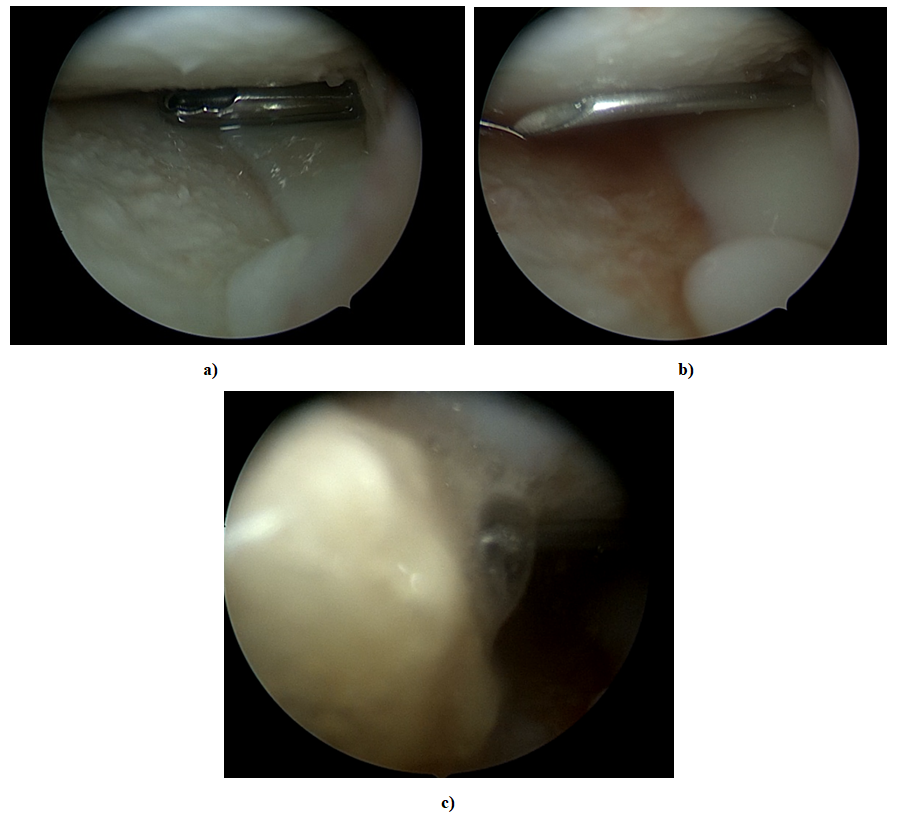

Figure 1. Arthroscopic view of cartilage condition and SVF injection into the knee joint under arthroscopic control. a)-removal of saline solution after arthroscopic debridement. b)-injection of a thick needle into the joint under arthroscopic control to inject SVF c PRP. c)-process of SVF c PRP injection into the joint